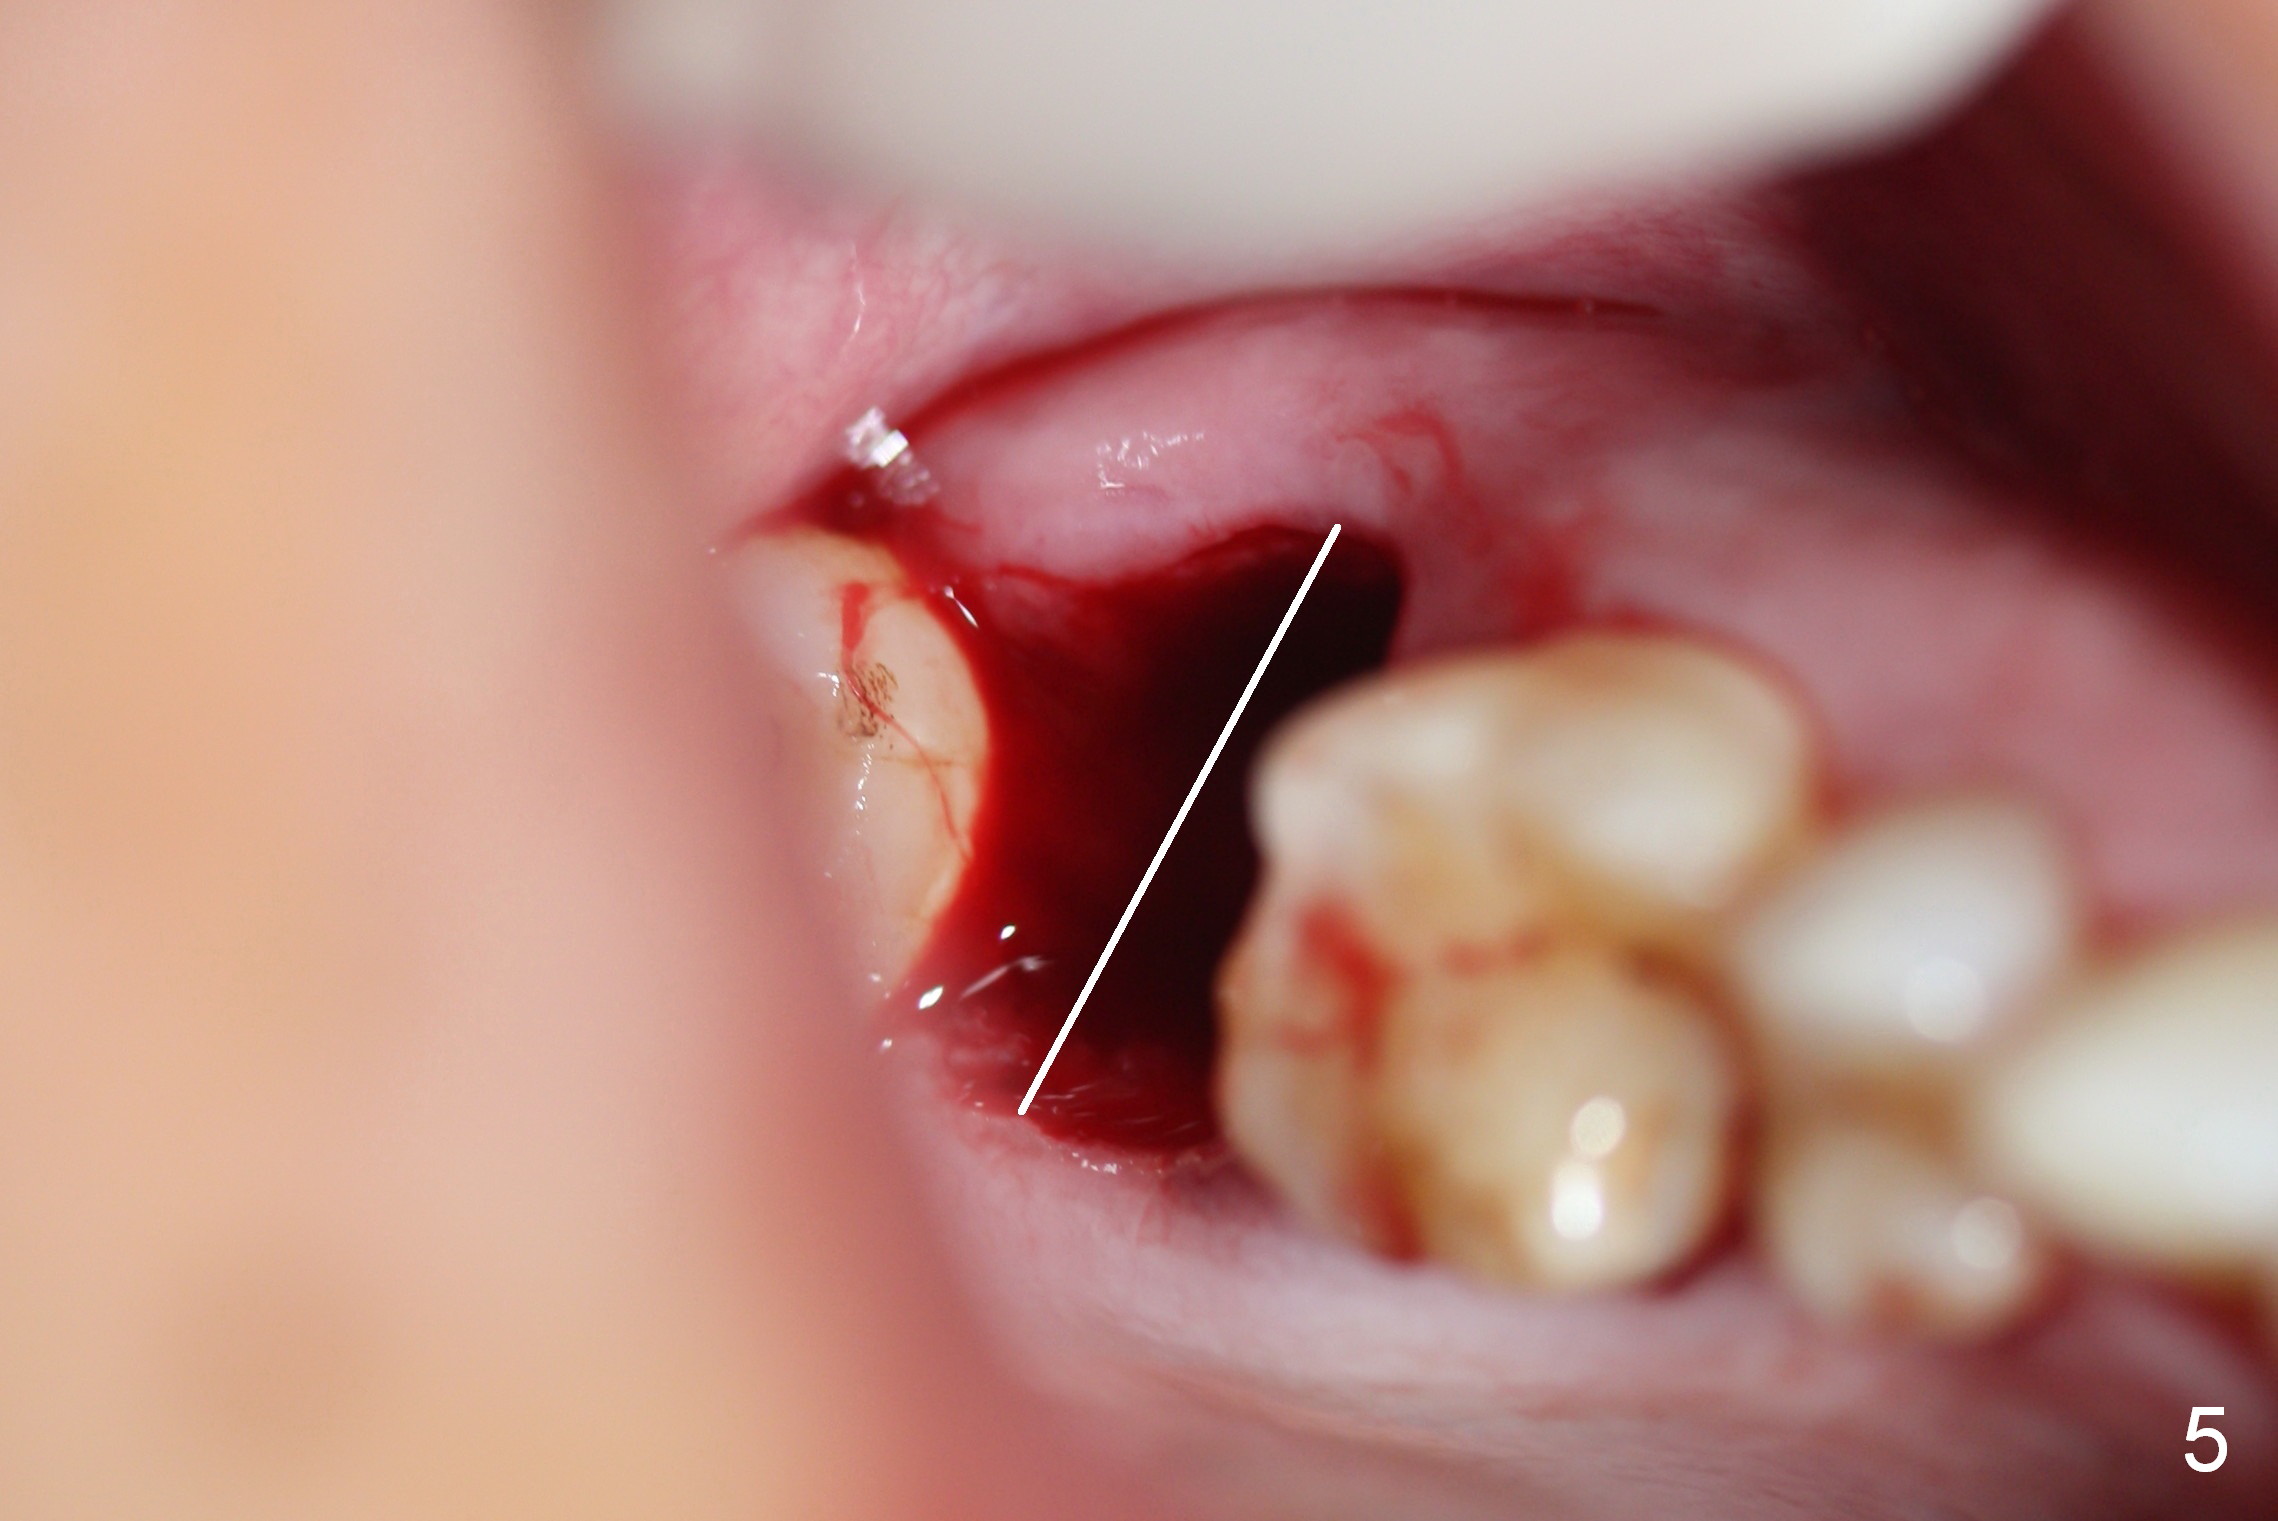

A 65-year-old lady is at early stage of Parkinson's disease and appears to be a bruxer. There are multiple chipped teeth, including #2 (Fig.1,4 *). She chooses implant over RCT retreat. A tissue-level implant (Fig.2) matches the root shape of the affected tooth better than a bone-level one (Fig.3), because of taper. The buccopalatal and mesiodistal dimensions of the extraction socket are 11 and 8 mm, respectively (Fig.5,7).

The buccal roots are fused. The buccal socket (BS) seems to be larger than the palatal one (PS). There is a septum (S) between the 2 sockets. Both the buccal and palatal plates (BP, PP) are intact. The anatomy is illustrated in Fig.6a (buccopalatal section) with the same abbreviations, mentioned above. SF: sinus floor.

Osteotomy for immediate implant is initiated with a 2 mm pilot drill (Fig.6b red arrow) in the coronal end of the buccal slope of the septum (center of the socket). Once the drill gets initial penetration, the trajectory changes to the long axis of the tooth (Fig.6c). Then PA is taken with a parallel pin (Fig.7). It appears that the depth is not enough; there is bone apical to the pin. As osteotomy increases in diameter, burs may be deviated buccally due to the septal buccal slope (to be discussed below). With longer osteotomy, the deviation may be less. Osteotomy is deepened (Fig.6d). From this moment on, nose blowing test is done after each step. The result is all negative. As drill diameter increases, they do deviate buccally (Fig.6e arrow), since there is less bone contact buccally than lingually (compare Fig.6e,f). With the same reason, smaller tapered taps (Fig.6g pink, 5 and 6 mm) tend to be mobile buccally (arrow). When a large tap (7 mm) is inserted (Fig.8), there is no buccal mobility. It appears that the tap contacts more of the buccal plate (Fig.6h), but the coronal end of the tap is buccal (Fig.6i, pink circle). At each step of osteotomy, the coronal end of a bur or tap should be pushed as lingual as possible so that the final tap is favorable for restoration (Fig.6j). Sinus lift is done (Fig.6k red circle; Fig.9 *) before placement of 7x17 mm implant (I, >60 Ncm). Since the palatal socket is not associated with implant stability, it is closed by collagen plug (Fig.6l, blue area). As extra precaution, bone graft is placed around the coronal portion of the tissue-level implant (Fig.6l red circles), followed by collagen dressing.